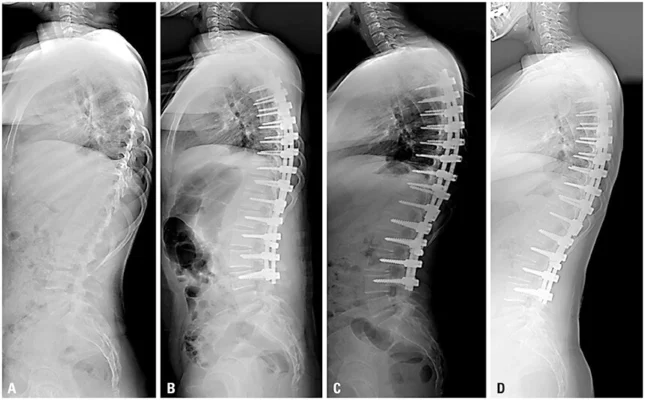

小児側弯症の事実と小児側弯症治療の方法

小児脊柱側弯症は、身長の変化や定期的な検査によって発見されることが多く、脊椎X線写真によって診断される。